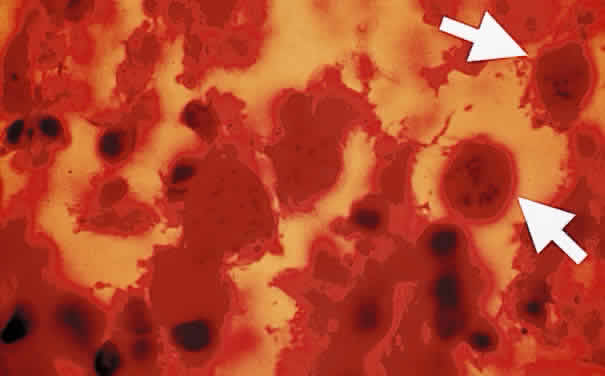

Tachyzoite is the proliferative form of the organism, which used to be known as trophozoite. It has a crescent shape and measures approximately 7 μm in length and 3 μm in width (Fig. 1). The organism is motile with a unique cytoskeletal structure allowing it to twist, wiggle, rotate, and glide. The rostrum of the tachyzoite is known as the conoid, which can extend, retract, tilt, and rotate. These movements allow the tachyzoite to find its target host cell and to penetrate the cell, establishing an intracellular existence. Tachyzoites are easily propagated in peritoneal cavities of mice and in mammalian tissue culture cell lines. The organism has the ability to replicate in all mammalian nucleated cells. In the host cell, the tachyzoite multiplies by endodyogeny; this reproductive process is susceptible to heat, freezing and thawing, desiccation, and gastric enzymes.

Fig. 1. Toxoplasma gondii. Tachyzoites from the peritoneal exudates of infected mice stained with Giemsa (× 100).